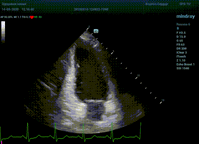

С появлением В режима реализовалась возможность визуализации всех сегментов миокарда из парастернальных и апикальных сечений. Метод Teicholtz в широкой практике сменился методом дисков. Метод дисков, или метод Simpson, позволяет разбить левый желудочек на 20 дисков, с расчетом объема каждого из них. Используя 2 перпендикулярных сечения, апикальные двух и четырех камерное, мы приближаемся к значению реального объема левого желудочка. Исследователь обводит интерфейс эндокард – кровь в фазу диастолы и фазу систолы. Линия простирается от кольца митрального клапана и до кольца митрального клапана, четко разграничивая объем желудочка от предсердия. Для достоверного изменения необходимо использовать ЭКГ канал.

Что могут предложить современные приборы? Приборы нашего времени являются мощными вычислительными машинами, способными обрабатывать полученную информацию даже без помощи человека. Система автоматического вычисления фракции выброса – AUTO EF на приборах серии Resona компании Mindray сделает все за вас. За пару секунд прибор сам отыщет нужную фазу сердечного цикла и произведёт измерение и расчеты, а также покажет график изменения объема в сердечном цикле. От Вас требуется только получить качественное 4С и 2С сечение. Впрочем, прибор всегда оставляет возможность коррекции, если доктор имеет свое мнение на расположение точек планиметрии или момента измерения по ЭКГ каналу.